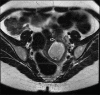

Figure 1a

MRI pelvis (axial image) – Uterus didelphys, normal endometrial cavity, normal ovaries, with large collection in left hemivagina